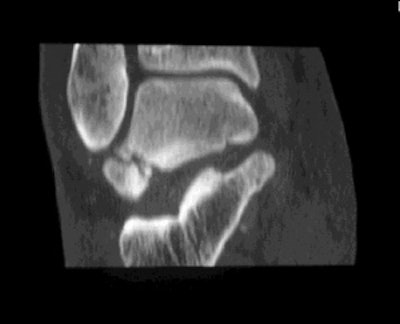

![]() |

| Axial CT scan shows that the largest fracture fragment is displaced 3-4 mm posterolaterally. The peroneal tendons (white arrow) do not appear to be affected by the fracture fragments. Images courtesy of Dr. Douglas Beall. |